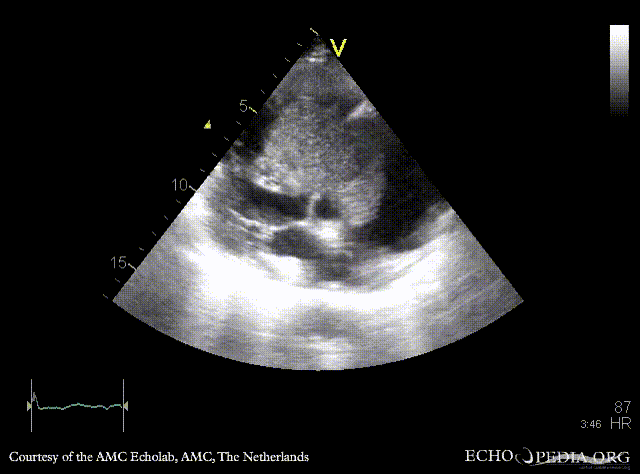

| Giant myxoma in right atrium

| PLAX: giant mobile myxoma in right atrium

| PSAX